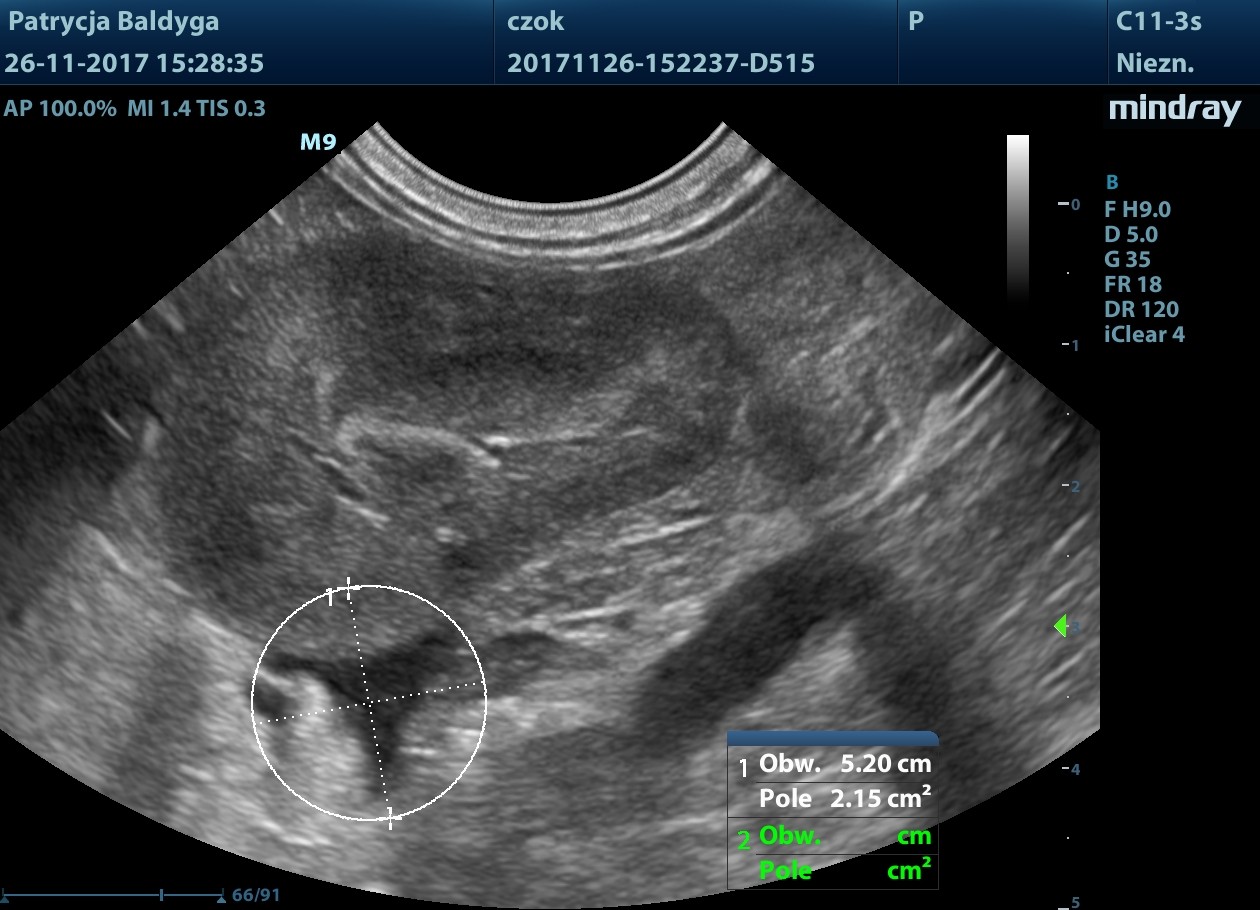

Miąższ szczególnie płatów lewych o miejscowo wzmożonej echogeniczności, nieco nieregularnej torebce, z obecnością zmiany ogniskowej najpewniej krwiaka pourazowego ok. 3,2 x 1,6 cm w płacie lewym bocznym modulującego znacznie torebkę powierzchni trzewnej.